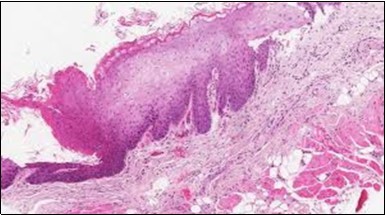

Figure 5.HCL: hairy cells with infiltration in the spleen(21).

Figure 6.HCL: disseminated hairy cells with a clear cytoplasm(22).

Figure 7.HCL: blebs on the cellular surface with fine nuclear chromatin(23).

Figure 8.HCL: widely disseminated hairy cells within the bone marrow trabaculae(24).

Figure 9.HCL: hairy cells within a bone marrow trephine biopsy(25).